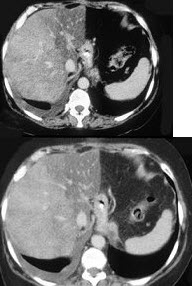

男,66岁,肥胖,有糖尿病史,CT检查如图,最可能的诊断是( )

A:局灶性脂肪肝

B:肝硬化肝癌

C:肝血管瘤

D:肝胆管细胞癌

E:肝淋巴管瘤